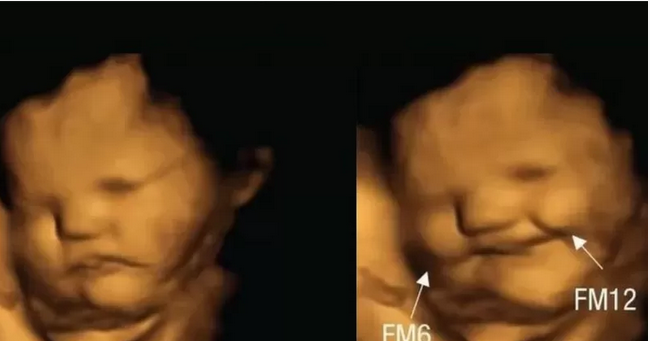

Daraasad ay dhawaan seynisyahanno ku sugan UK ku sameeyeen 100 haween ah oo uur leh iyo ilmaha calooshooda ku jira ayaa lagu ogaaday in marka ay hooyada xaamilada ah cunto karooto ay ilmaha uurkeeda ku jira ”dhoolla-caddeeyaan” marka ay khudaarta cagaaran cuntana ”aysan ku farxin”.

Kooxda seynisyahannada ah ee daraasaddan soo saaray ayaa waxa ay Majalladda ka faalloota Seyniska Cilmi-nafsiga ku qoreen in 20 daqiiqo kaddib markii hooyooyinka uurka leh la siiyay karootada ay raajooyinka laga qaaday sawirradooda muujiyeen inay ku farxeen, ayna dhoolla-caddeynayeen.

Ilmaha ay gaadhay saameynta budada khudaarta kabashka ayaan ku farxin dhadhankaas, waxaana sawirradooda wajiga ka muuqatay in ay caroodeen.

Sawirrada ayaa lagu qaadayay raajooyinka casriga ah ee loo yaqaanno ”4D ultrasound”.